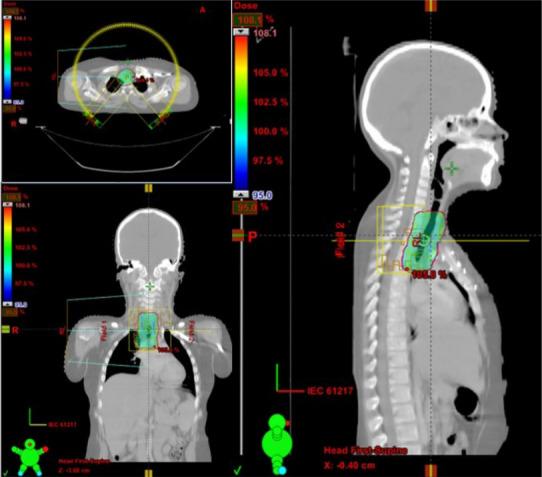

黏液表皮样癌(MEC)是成人小涎腺最常见的恶性肿瘤。肺黏液表皮样癌极为罕见,仅占原发性肺恶性肿瘤的0.1%-0.2%,占原发性支气管肿瘤的比例不到1%。在儿童中更为罕见,文献报道仅限于少数病例。在此,我们报告一例9岁男孩诊断为原发性气管黏液表皮样癌的病例,并对相关文献进行回顾。一名9岁男童主诉干咳两年,一年后出现气短。支气管镜检查发现隆突右侧壁有一肿物,阻塞管腔50%,详细的组织病理学检查显示为气管黏液表皮样癌。患者接受了肿瘤局部切除及一期吻合术。鉴于切缘阳性,对瘤床给予60 Gy分30次的辅助放疗。患者对治疗耐受性良好,随访6个月无疾病复发。儿童气管黏液表皮样癌的治疗经验有限,尚未确定最佳治疗方案,目前的治疗主要是借鉴涎腺黏液表皮样癌的治疗方法。